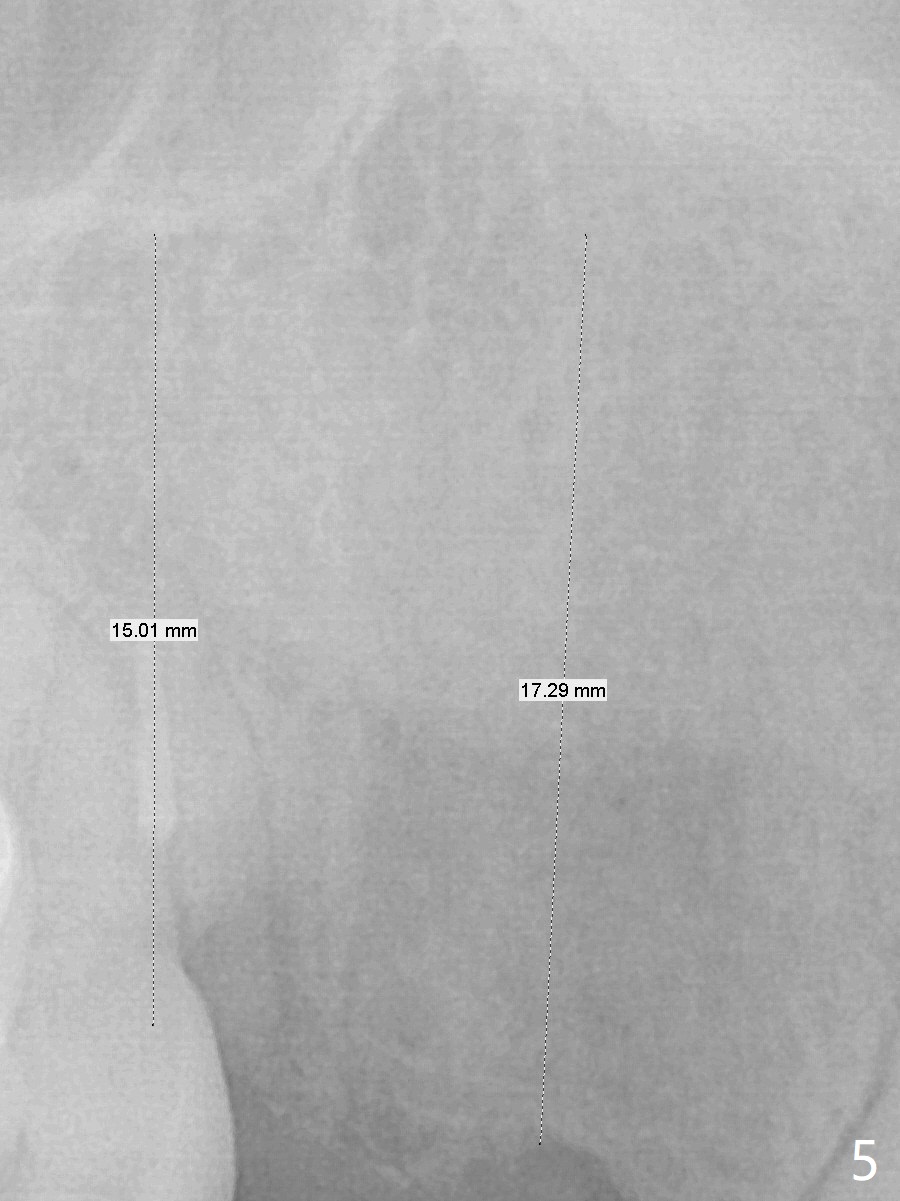

A 38-year-old skinny woman has several missing teeth (Fig.1). Recently a #6-7 cantilever FPD dislodged (Fig.2,3). The buccal plate at #6 must be thin. Socket shield should be indicated, particularly when extraction turns out to be difficult. A 4x13 mm IS implant is going to be inserted as distal as possible to avoid touching the apex of the tooth #5 (Fig.4,5). Since the ridge at #7 is narrow, a 1-piece implant will be placed (possible 2.5x14(2) mm, Fig.5). Take PA after the 1st drills. Take preop photos to show the residual root at #6 and the narrow ridge at #7.